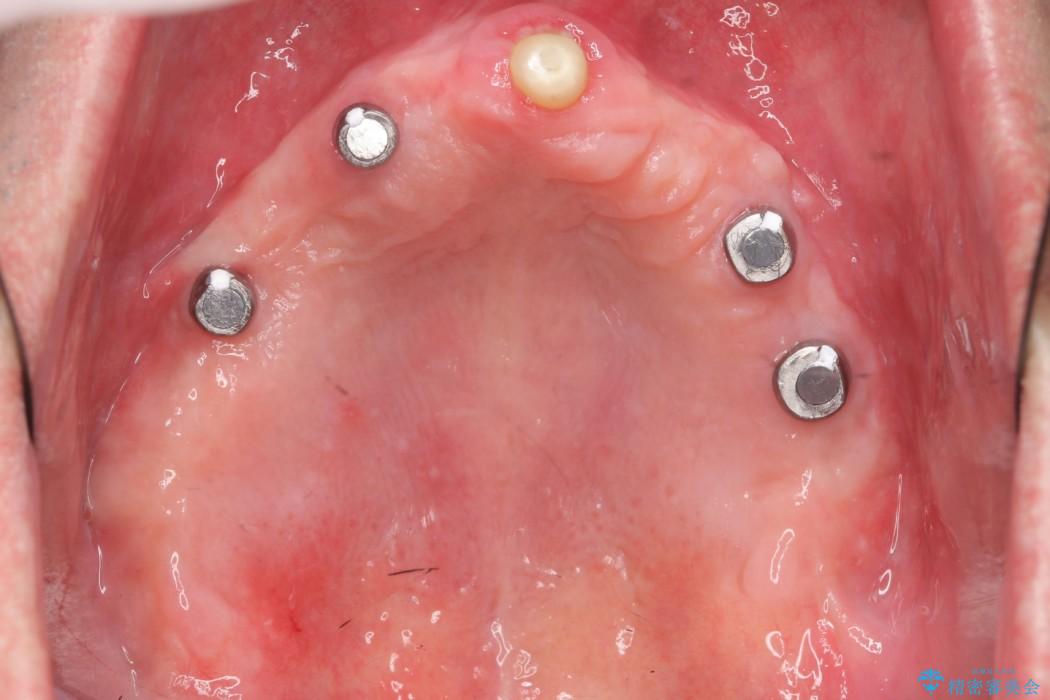

状態から残せないと判断した歯を抜歯、噛み合わせ回復のため土台にインプラントを用いた上顎義歯にて補綴治療をすることとしました。

本症例では失った歯を補うため、マグネットを使用したインプラントの入れ歯(マグネットオーバーデンチャー)という維持機構を使用しました。

マグネットタイプは無理な側方力がかかると入れ歯が外れるため、口腔内に設置する装置が他の維持装置と比べてインプラント体や支台歯へ大きな負担がかかることを防止してくれます。

また着脱が簡単であり、磁石の固定によりガタつかず非常に安定します。